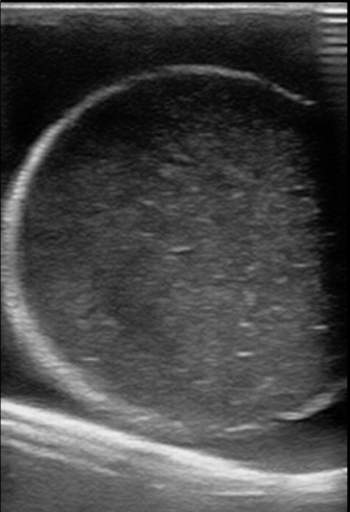

Figure 11. A model with normal testicle and a hydrocele.